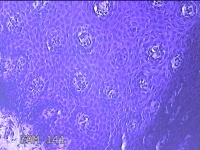

口腔黏膜肿物

性别

男

年龄

33岁

临床诊断

口腔黏膜肉芽肿

一般病史

无

标本名称

大体所见

灰白粉红色肿物0.8x0.5x0.3cm一个,表面糜烂。